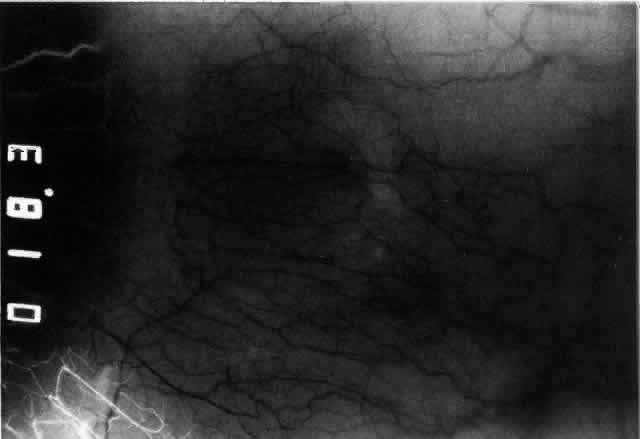

Simple and nodular episcleritis differ in their clinical courses, but in both the edema and infiltration are entirely within the episcleral tissues. The sclera is not involved. The maximum congestion is in the superficial episcleral network, with some slight congestion of the conjunctival vessels and deep episcleral vessels (Fig. 10). The intraocular structures are not involved in either variety, nor is the visual acuity affected. Anterior segment fluorescein angiography reveals a normal vascular pattern but a very rapid flow rate, with the whole transit of the dye being completed within 2 or 3 seconds (Figs. 11 and 12).

Fig. 10. Maximum congestion in the superficial vascular plexus in episcleritis. The conjunctival and deep episcleral networks are separated from the deep plexus by edema and infiltration in the episcleral tissue. (Watson PG, Hayreh S, Awdry P: Episcleritis and scleritis. Br J Ophthalmol 52(3):278–279, 1968)

Fig. 11. Anterior segment fluorescein angiogram of a 45-year-old woman with simple episcleritis. At first transit of dye, all the vessels are dilated and filling simultaneously. However, the vascular pattern is not disturbed.

Fig. 12. Angiogram of the same 45-year-old woman in Figure 11 one second later. Within 1 second, all the vessels are filled and there is even, venular filling except in the deep episcleral plexus. This is the rapid filling pattern seen in all forms of episcleritis and in diffuse anterior scleritis.

The redness of simple episcleritis may be intense, varying from a fiery-red or a brick-red discoloration to a mild red flush, but it does not have the bluish tinge that is seen in scleritis. The distribution is usually sectorial but can involve the whole anterior segment of the globe. The episcleral vessels are engorged but retain their normal radial position and architecture (Figs. 13 and 14; Color Plate 1A). In simple episcleritis, there is a diffuse edema of the episcleral tissues. These tissues are sometimes infiltrated with gray deposits that appear yellow in red-free light. Surprisingly, the eye is rarely tender to the touch.